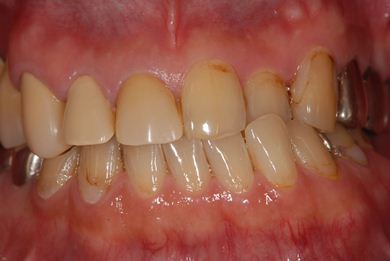

| 性別/年齢 | 男性 / 53歳 | ||||||||||||||||||||||||||||||||

| 主訴 | 左下奥歯2本のインプラント治療を希望。 | ||||||||||||||||||||||||||||||||

| 治療方針 | 左下欠損部分をインプラント治療にて機能的・審美的回復を行う。 | ||||||||||||||||||||||||||||||||

| 治療内容 | インプラント2本、ハイブリッドセラミッククラウン2本 | ||||||||||||||||||||||||||||||||

| 総治療費 | 399,000円 | ||||||||||||||||||||||||||||||||

| 治療期間 | 9ヶ月 |